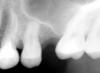

Сходила на Air flow. Заодно проконсультировалась по поводу коронки на четверку. Сделала снимок (верх). После чистки семерка (на снимке второй справа) начал реагировать на холод. Семерка под пломбой. Раньше проблем не было. Можно ли по снимку понять - есть там кариес или нет? Или это нормально после процедуры Air Flow? Ни десны, ни остальные зубы никак не прореагировали на чистку.

Если боль от холодного сразу проходит, то скорее всего связано с Аэрофло(оголилась шейка зуба) Пройдёт. Если ноет потом некоторое время, то пульпит может быть.